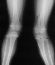

XRAY:

X-ray Set 1. 10 Months post Fracture, Right 8* Left 19* Mechanical axis

X-ray Set 2. 16 Months post Fracture, Right 8* Left 26* Mechanical axis, Left 34* Femoral Tibial Angle.